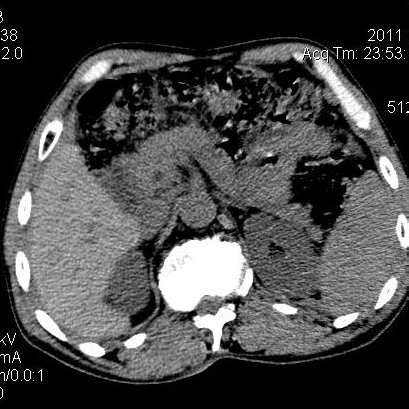

肝左叶发育异常

男性,55岁,骑摩托车摔倒后入院,自述右上腹疼痛

[backcolor=#FF0000]第一次诊断的时候也是这么肯定,可是床旁超声检查并没有发现明显异常,而且患者的一般症状都良好。还好临床只是保守治疗,没有立即手术,第二次复查的时候没有一点变化,又做了MRI检查,没有血肿,

这是一例肝左叶发育异常的,很个性吧~[/backcolor]